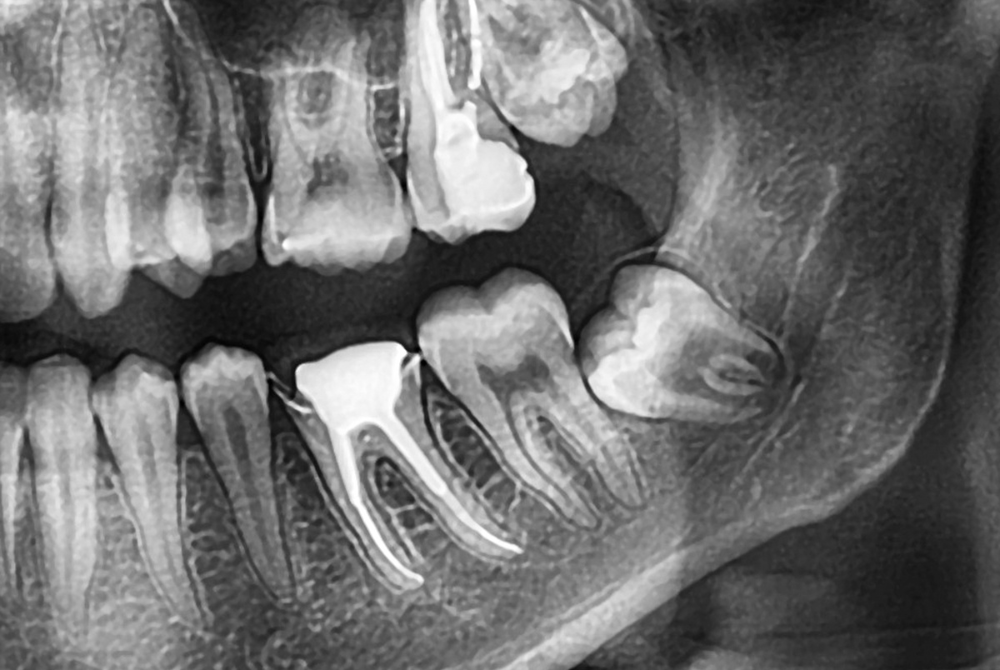

最初にお口の状態を確認し、レントゲン撮影を行って親知らずの向きや根の形をチェックします。特に下の親知らずは神経が近いこともあるため、「簡単に抜けるタイプか」「切開が必要か」などをここで見極めます。抜歯の難易度や時間の目安も、この検査の結果で説明されます。